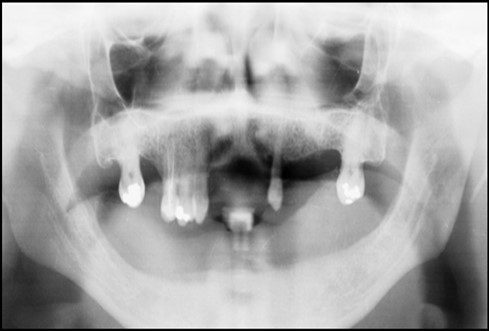

A 63 year old male patient came to our Aesthetics Dental Clinic ,Athens, Greece with the chief complaint of loose fitting lower denture with difficulty in mastication and speech. On examination, patient had resorbed alveolar ridge which lead to inadequate retention of the lower denture prosthesis and patient is known to be a previous denture wearer for past 1 year. The Orthopantomograph findings showed the presence of sufficient bone height and width (Figure 1), with dense cortical bone surrounded by dense trabecular bone. Thus implant supported overdenture was planned with two implants along with independent ball type attachments.

Figure 1.First Visit Pre-operative radiograph